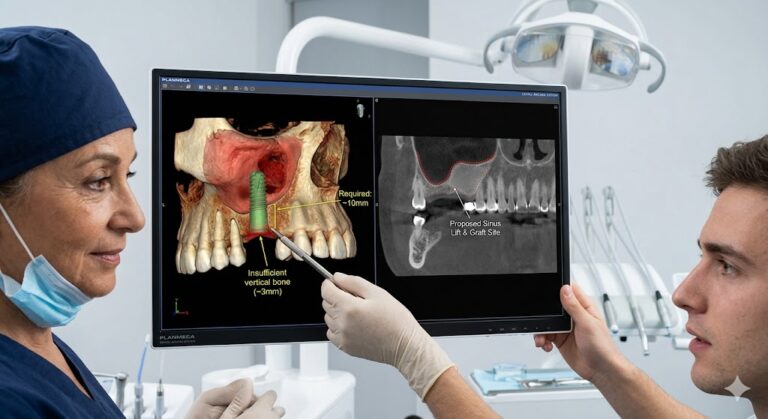

Major Grafting (Block Graft or Sinus Lift)

If you have been missing a tooth for years, your bone may have resorbed (melted away). A sinus lift for upper molars or a block graft from your chin or hip can take 45 to 90 minutes. The implant is not placed on the same day. You wait 6 to 9 months for the graft to mature into solid bone.

- Get a CBCT scan (3D X-ray). This gives the surgeon a virtual roadmap. No surprises means faster drilling.